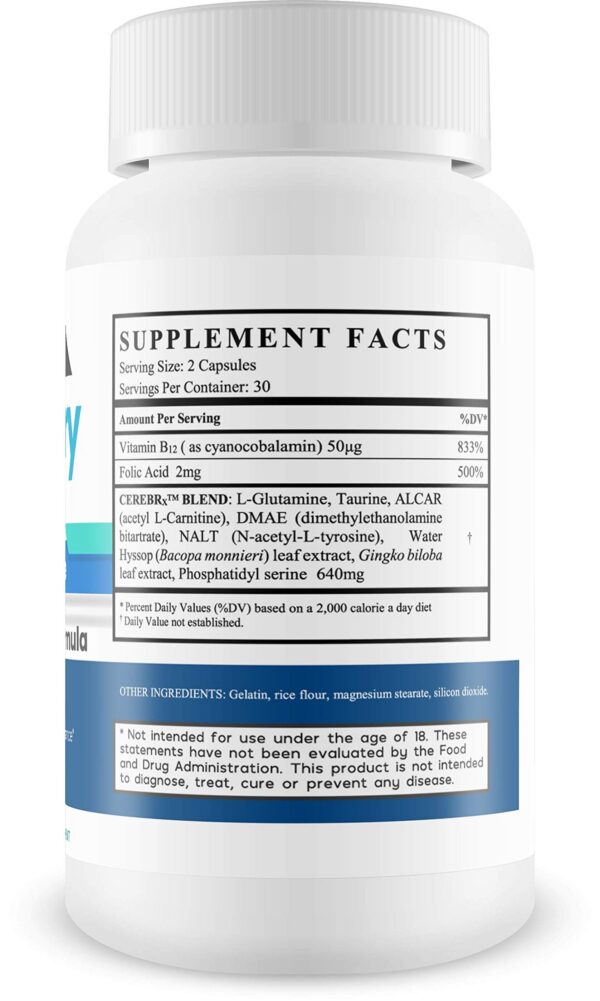

Tamaño: 1 cápsula

Peso del producto: 45 g

- FÓRMULA NATURAL CON MEZCLA CerebRx patentada y otros ingredientes.

- MEZCLA NOOTRÓPICA DE ACCIÓN RÁPIDA, diseñada para una combinación equilibrada de ingredientes.

- INCLUYE TAURINA Y OTROS INGREDIENTES NATURALES.

Memory Hack es una fórmula natural para el cerebro.Contiene Taurina y otros ingredientes naturales como parte de la mezcla CerebRx.Diseñada para uso diario.